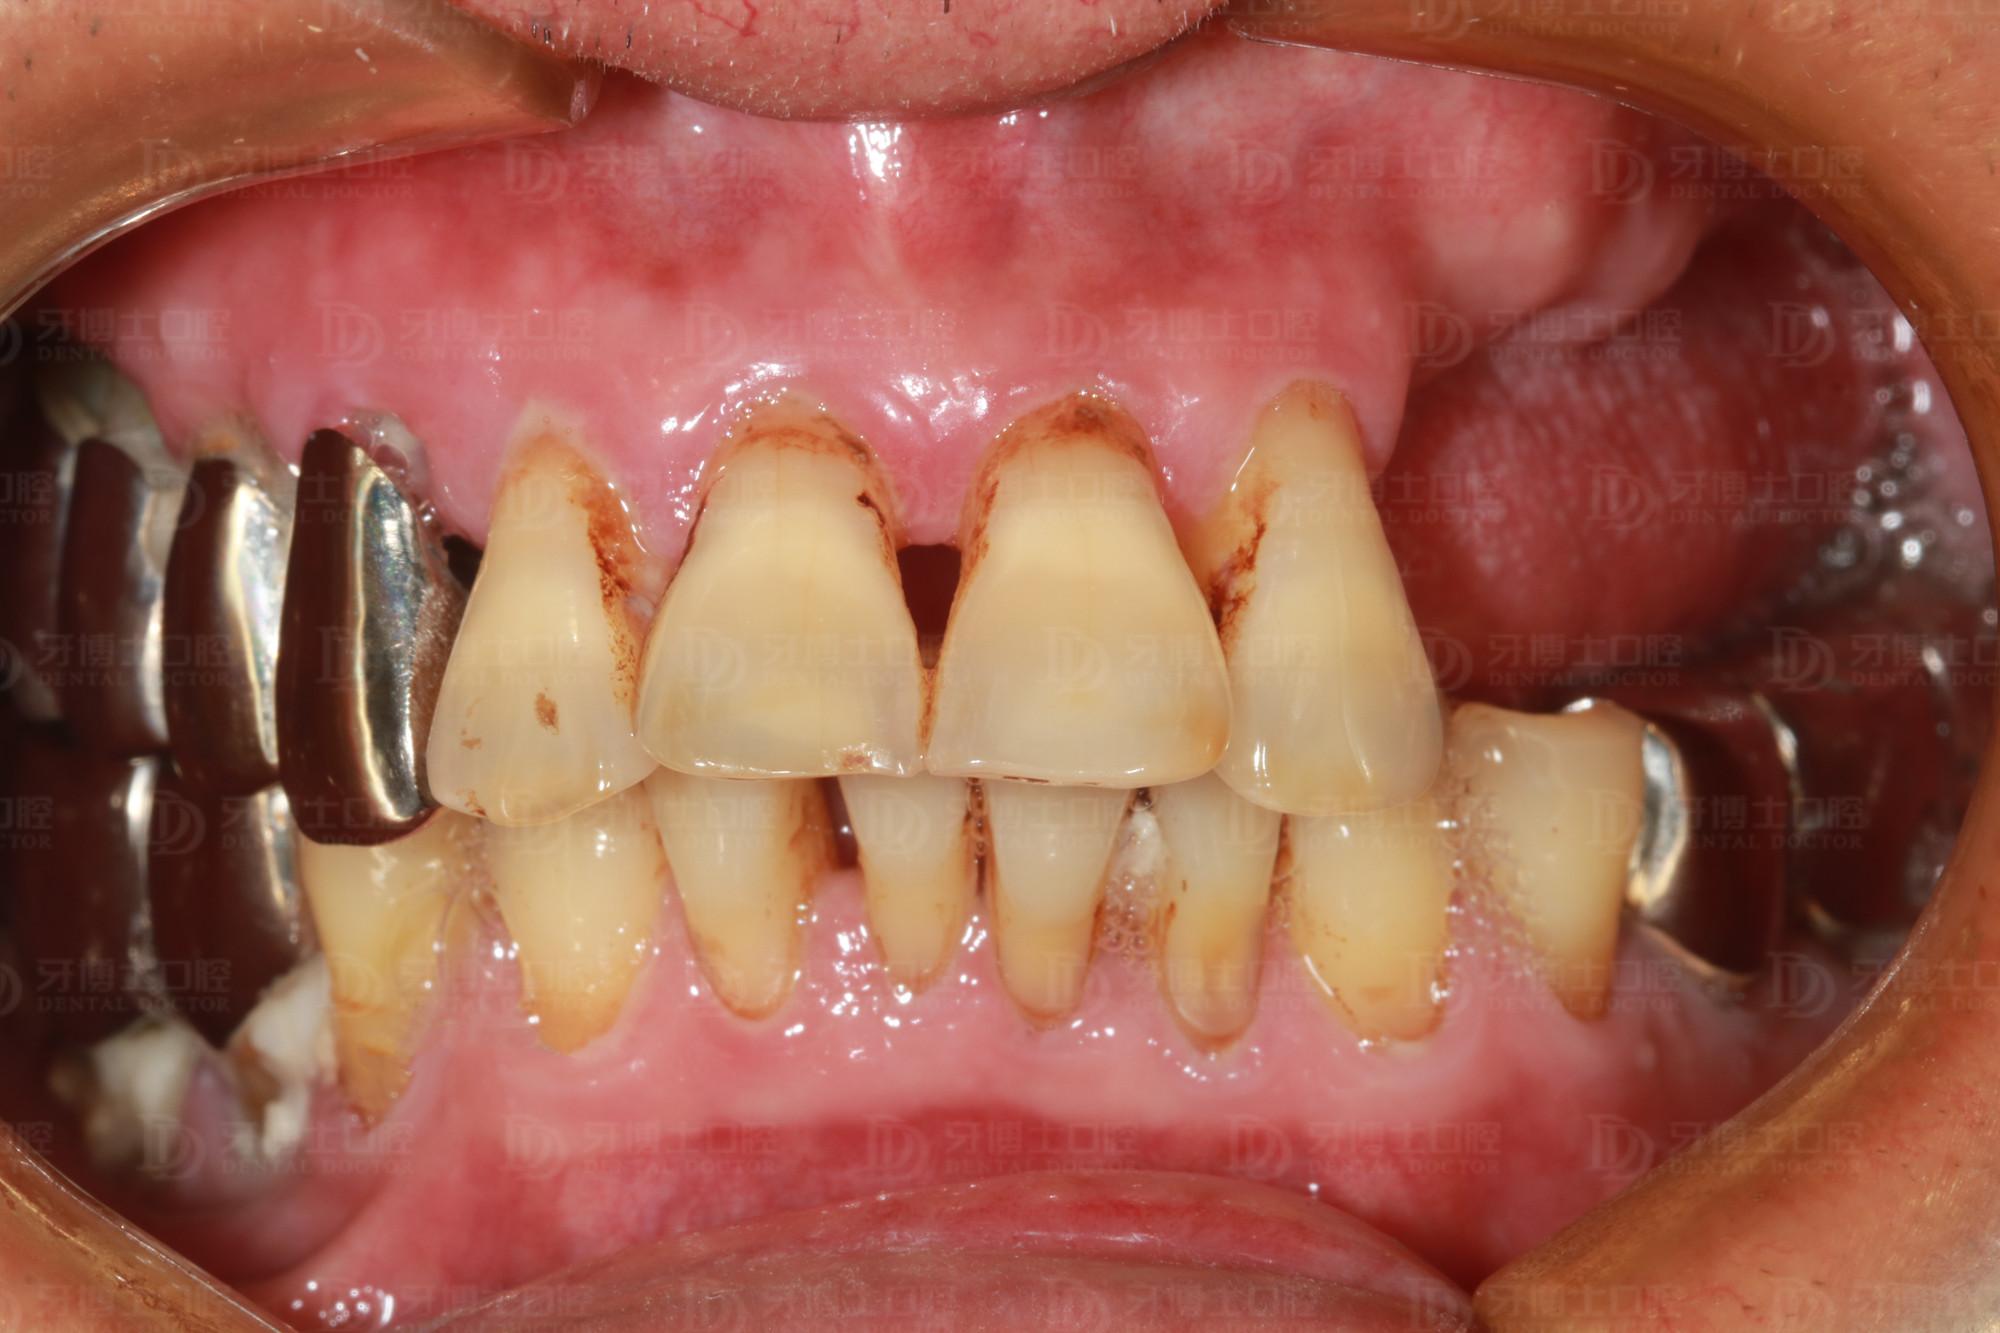

年近七旬的周老爺子(化名)牙齒缺失多年,上排牙只剩4顆前牙。前些年做的一側(cè)不銹鋼牙松得厲害,因?yàn)殚L(zhǎng)期用那一側(cè)牙咀嚼,導(dǎo)致牙齒的牙根全部咬壞掉了,醫(yī)生開玩笑說“你這牙很脆弱了,打個(gè)噴嚏就會(huì)掉下來”。

據(jù)醫(yī)生介紹,像周老這種情況在臨床上很常見,后邊大牙缺失,咀嚼時(shí)前面三顆牙帶后面兩顆牙,咀嚼時(shí)間久了,形成杠桿作用,加上前面牙齒又負(fù)荷過重,牙根就全部斷掉了,只能拔除。

種牙前